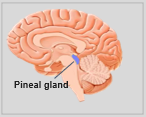

Die Neuroanatomie ist das Teilgebiet der Anatomie, das sich mit der Anatomie des Nervensystems befasst, d. h. mit der Struktur, Funktion und Organisation des Nervensystems. Das Nervensystem ist eines der komplexesten Systeme im menschlichen Körper und umfasst das Gehirn, das Rückenmark, die peripheren Nerven und die Nervenganglien. Die Neuroanatomie befasst sich damit, wie diese Strukturen miteinander verbunden sind, wie Signale zwischen den Nervenzellen übertragen werden und wie die verschiedenen Teile des Nervensystems zusammenarbeiten, um körperliche und kognitive Funktionen zu steuern. Neuroanatomen verwenden fortschrittliche bildgebende Verfahren wie Magnetresonanztomographie (MRT), Positronenemissionstomographie (PET) und Mikroskopie, um die Strukturen und Funktionen des Nervensystems sichtbar zu machen.